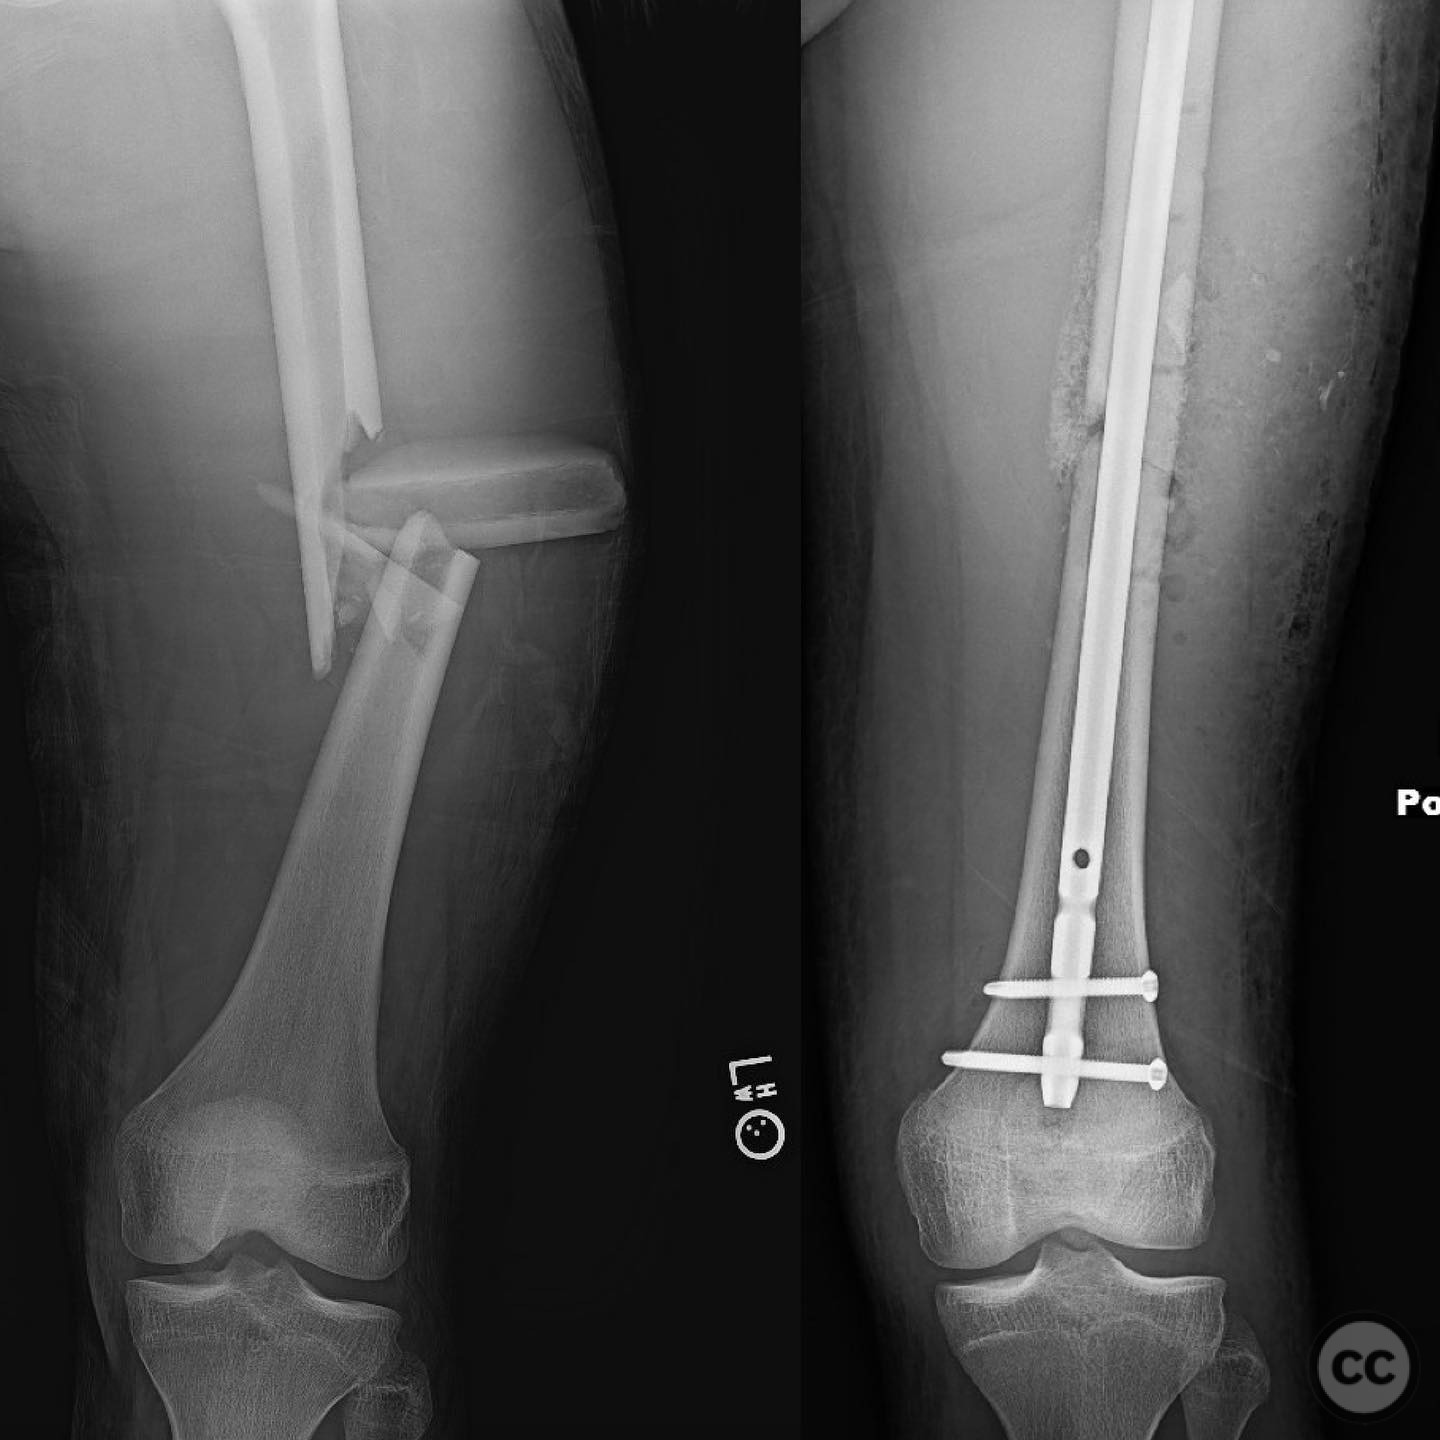

Orthopaedic implants used:   Intramedullary nail, autologous bone graft from reamings.

The surgeon noted that indirect reduction techniques were inadequate due to the fracture's complexity, necessitating an open reduction. Emphasis was placed on preserving fracture biology by minimizing periosteal stripping and avoiding suctioning of the medullary hematoma. Reamings were used as autograft material around the fracture site to enhance healing.

Postoperative protocol:   Postoperative rehabilitation included early mobilization with toe-touch weight-bearing (TTWB) for 6 weeks, followed by progressive weight-bearing as tolerated. Range of motion exercises were initiated early to prevent joint stiffness.